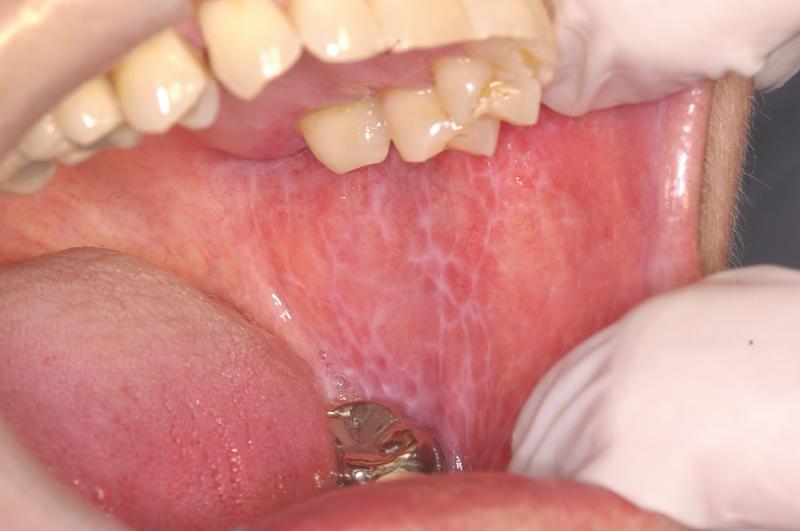

Descripción del caso Un varón de 57 años refiere que hace seis meses empezó a sentir molestias en el lado derecho de la lengua, que han ido en aumento y actualmente le...